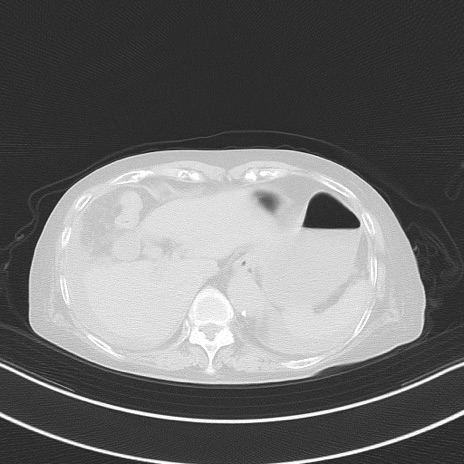

他院CT